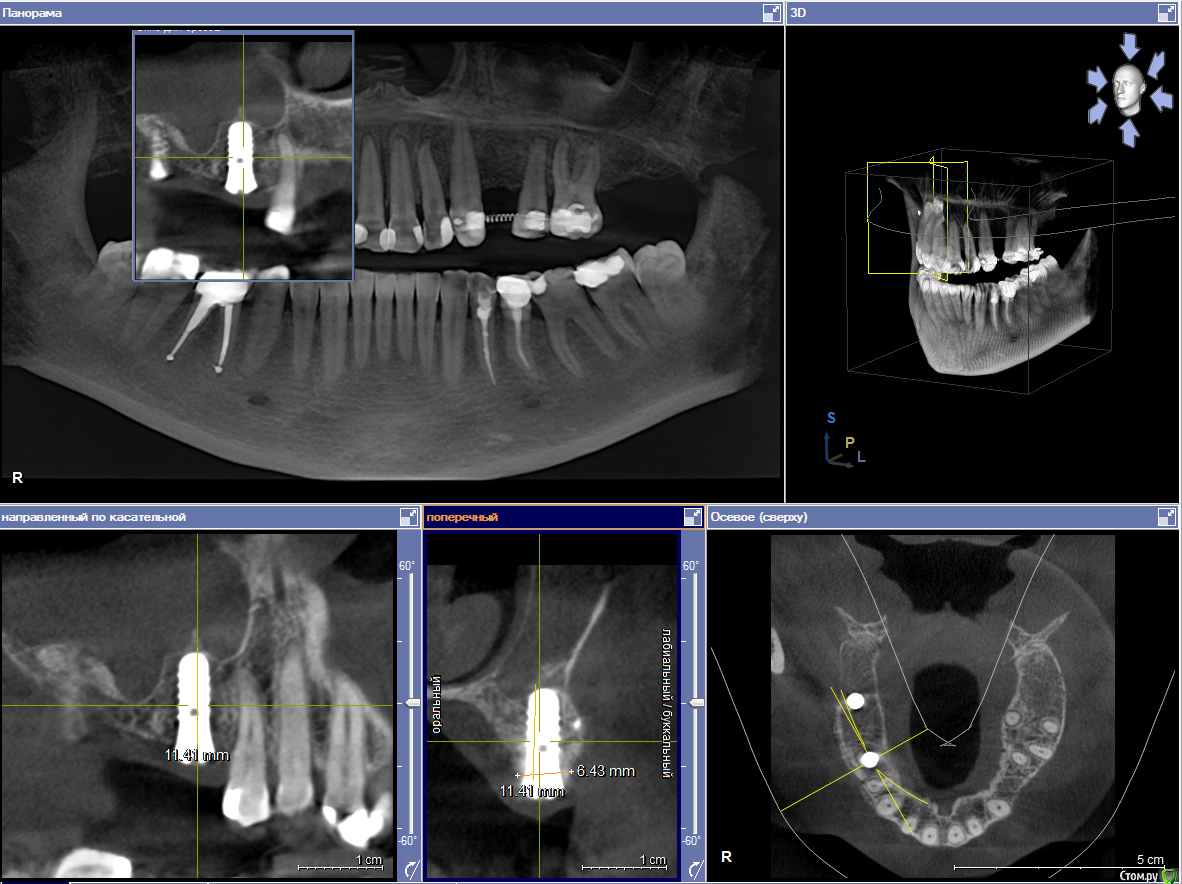

Пациентка пришла с целью восстановления отсутствующих 15,16,17,24,27 з.

Из анамнеза - хронический двухсторонний синусит, соответствующие зубы удалены более 5-ти лет назад, тетрациклиновые зубы ( от изменения цвета отказалась ).

Хирургический план :  консервативное лечение у ЛОР специалистов

1) имплантация в позиции 15,17 з с закрытым синусом и незначительной НКР

2) коррекция слизистой в области 1-го сегм

3) имплантация с ССТ в позиции 24 з ( после дистализации 25,26 з), в области 27 з на момент  операции был гнойный синусит, отложили